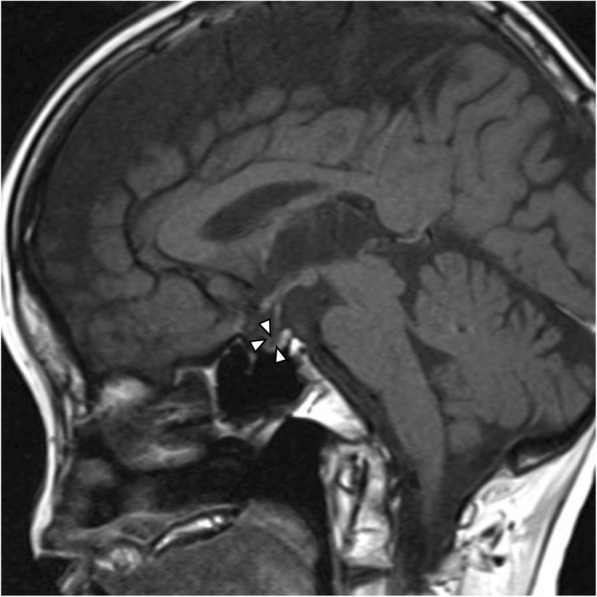

Fig. 2.

Hypothalamic-pituitary MRI image. A sagittal T1-weighted image is shown, confirming an empty sella turcica. No abnormality in the hypothalamus-pituitary stalk is evident, and a high-intensity signal is present in the posterior lobe. The anterior lobe is atrophic. Arrowheads indicate an empty sella turcica